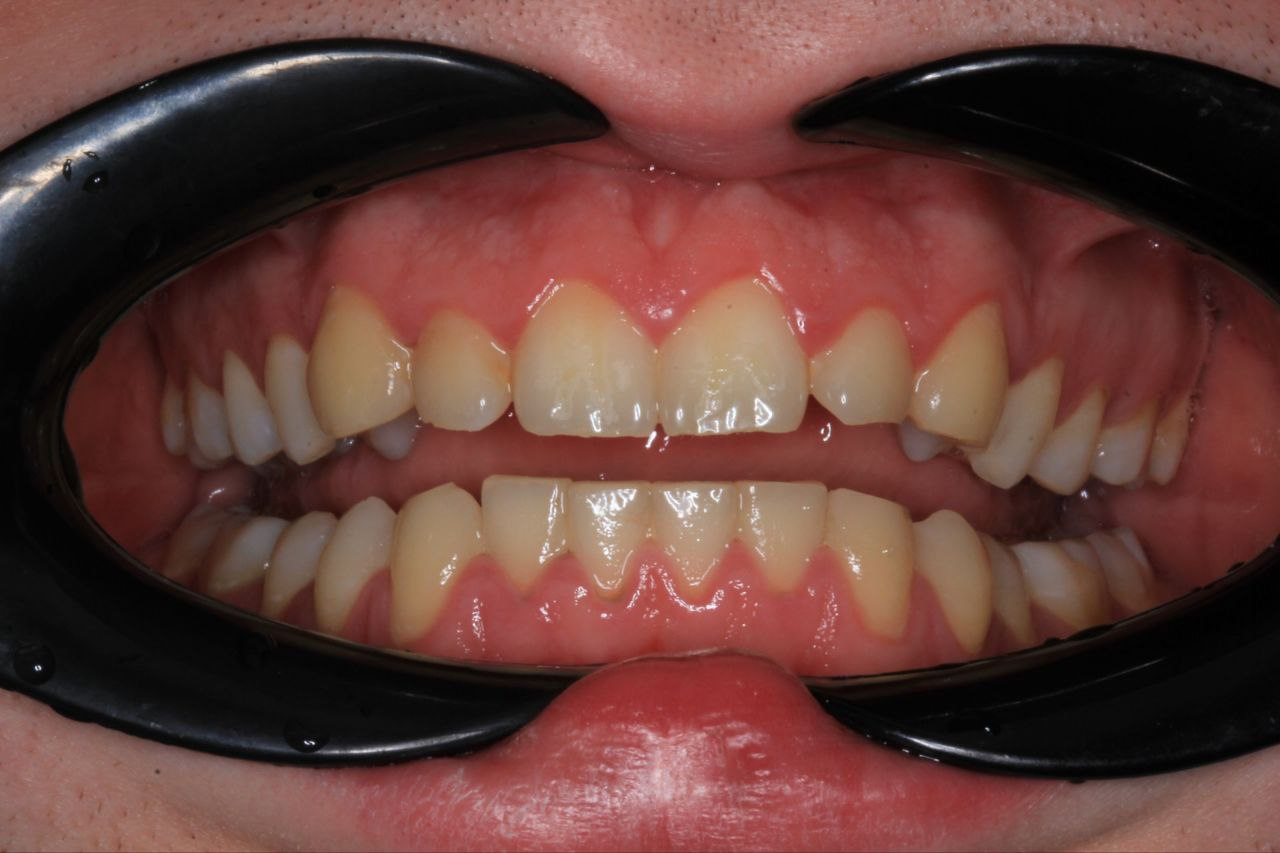

>>1631979 (OP)

сап двач

удалил зубы мудрости в 16 году, а в 17-18 носил брэкеты

жевательные зубы встали в шахматном порядке типо как надо, а вот середина верхней и нижней челюсти не совпадают, ортодонт сказал что все типо ок, сейчас меня начали терзать смутные сомнения - скажите это действительно ок или мне надо бежать к другому и заново выравнивать челюсти по нормальному?